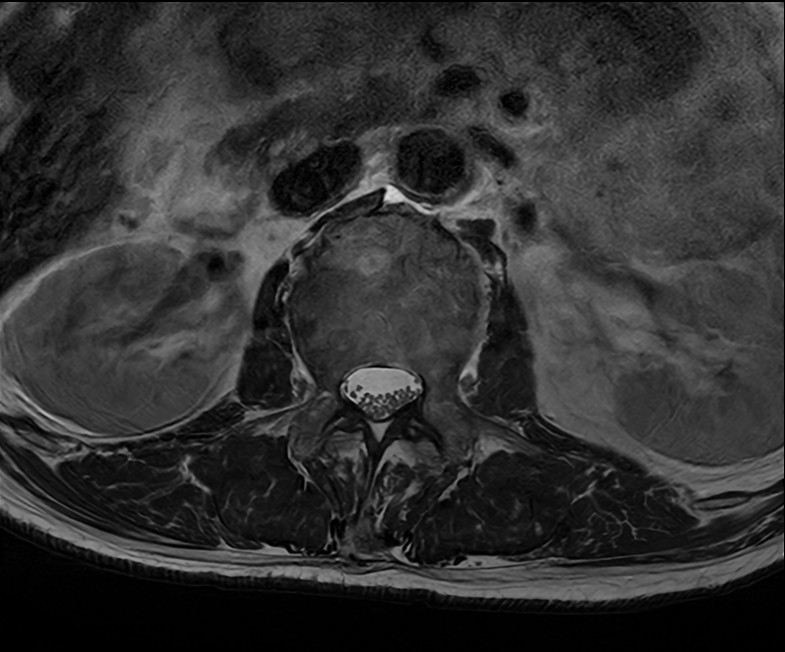

Axial T2w TSE